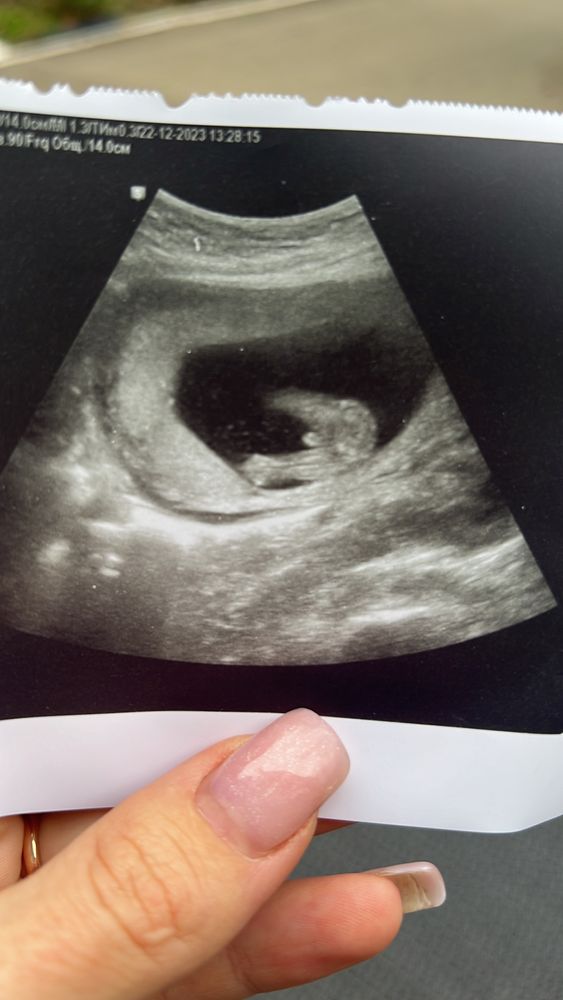

итак у нас будет пацан 2+2))))две девочки и два мальчика. Поровну теперь) хотя пророчили все девочку)

из плохих новостей. В моих водах Маша нашла муть. Или как там это называется. Осадок короче по краям (((( говорит что это не очень хорошо, может инфекция какая, может то что болела на 7 недели. Сказала что миомы нет. Это тонус матки к низу дает расширение и такой эффект. С ребенком все хорошо 🥰 но надо выяснять что это такое там в околоплодный водах.

ну и фото подтверждения вид с низу 😅